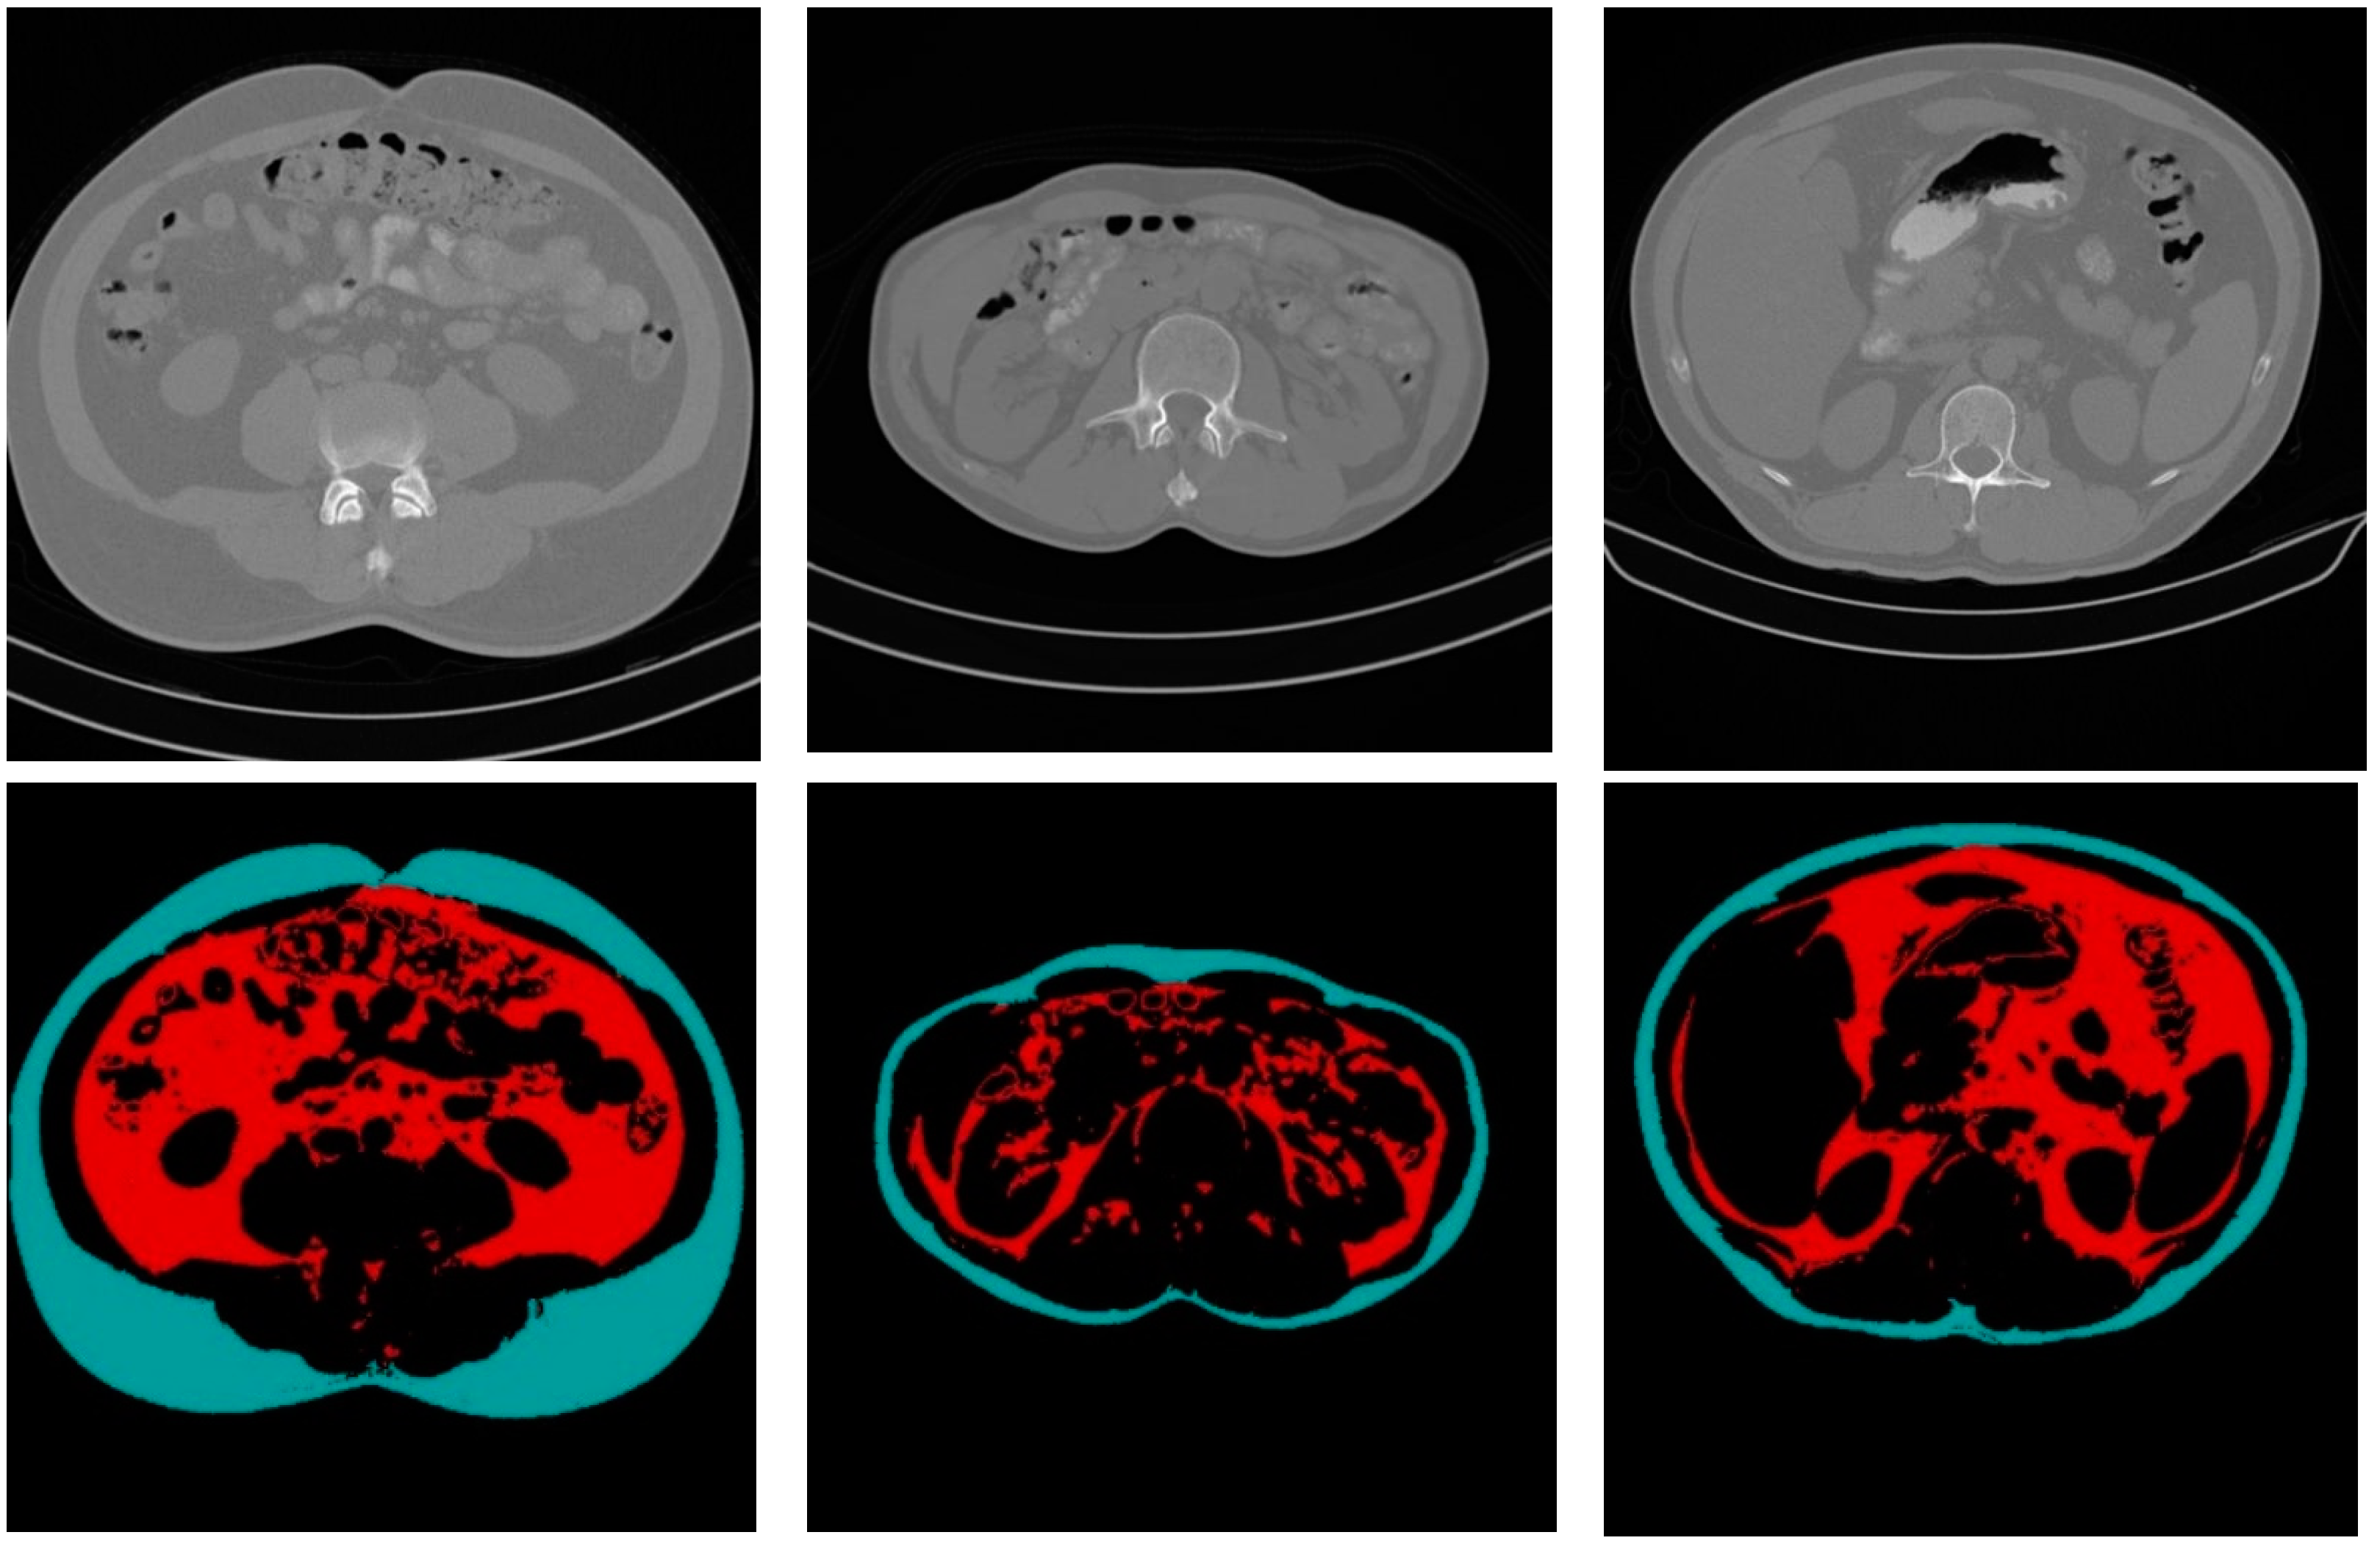

The fat classification method started by segmenting the SF from the fat binary image by applying element-wise logic and operation between the fat binary image and the inverse of the filled abdomen wall boundary image. Subtracting the SF binary image from the fat binary image produced a binary image where foreground pixels represented the VF. Figure 9 shows the steps of the classification process illustrated by an example.

Figure 10 shows some CT sample images and the results of fat segmentation and classification. The top row images are the original DICOM images, and the bottom row presents the results of fat segmentation and classification for the top DICOM images. The red color region represents the VF tissue, and the turquoise color region represents the SF tissues.

Figure 9. SF and VF classification operation.

Figure 10. Samples of the original CT images and the results of fat segmentation and classification.